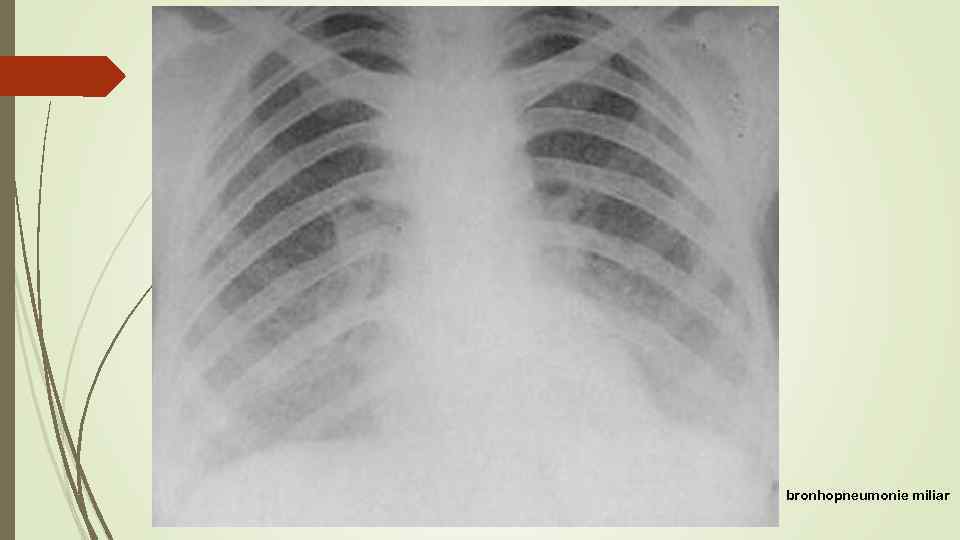

bronhopneumonie miliar

bronhopneumonie miliar

metastaze miliare

metastaze miliare